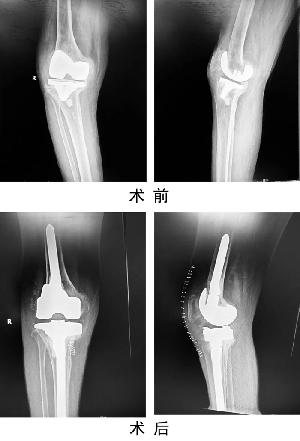

我院成功開展人工關(guān)節(jié)假體周圍感染一期翻修手術(shù)

關(guān)節(jié)運(yùn)動(dòng)醫(yī)學(xué)二科蘇長(zhǎng)征團(tuán)隊(duì),在我院首次成功開展人工膝關(guān)節(jié)假體周圍感染一期翻修術(shù),標(biāo)志著我院關(guān)節(jié)置換手術(shù)技術(shù)又上新臺(tái)階?;颊?,女,69歲,因“右膝人工關(guān)節(jié)置換術(shù)后6年,疼痛伴活動(dòng)受限1年”入住關(guān)節(jié)運(yùn)動(dòng)醫(yī)學(xué)二科。術(shù)前X線示右膝人工關(guān)節(jié)假體松動(dòng),感染指標(biāo)檢查:C反應(yīng)蛋白80mg/L,血沉20mm/h,關(guān)節(jié)穿刺培養(yǎng)提示表皮